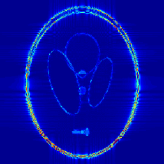

where J1subscript𝐽1J_{1} is the first kind Bessel’s function of order 111. Then using the variable density random sampling method in [46], we generate 20%percent2020\% undersampled k-space data. The complex white Gaussian noise is also added so that the resulting SNR of the samples is approximately 25dB25dB25\mathrm{dB} (See Fig. 3).

Refer to caption

(a) Fully sampled

(b) Ground truth

(c) Sample mask

(d) Undersampled

Figure 3: Dataset for the phantom experiments. Fully sampled k-space data, its inverse DFT as a ground truth, the undersampling mask, and the undersampled k-space data.